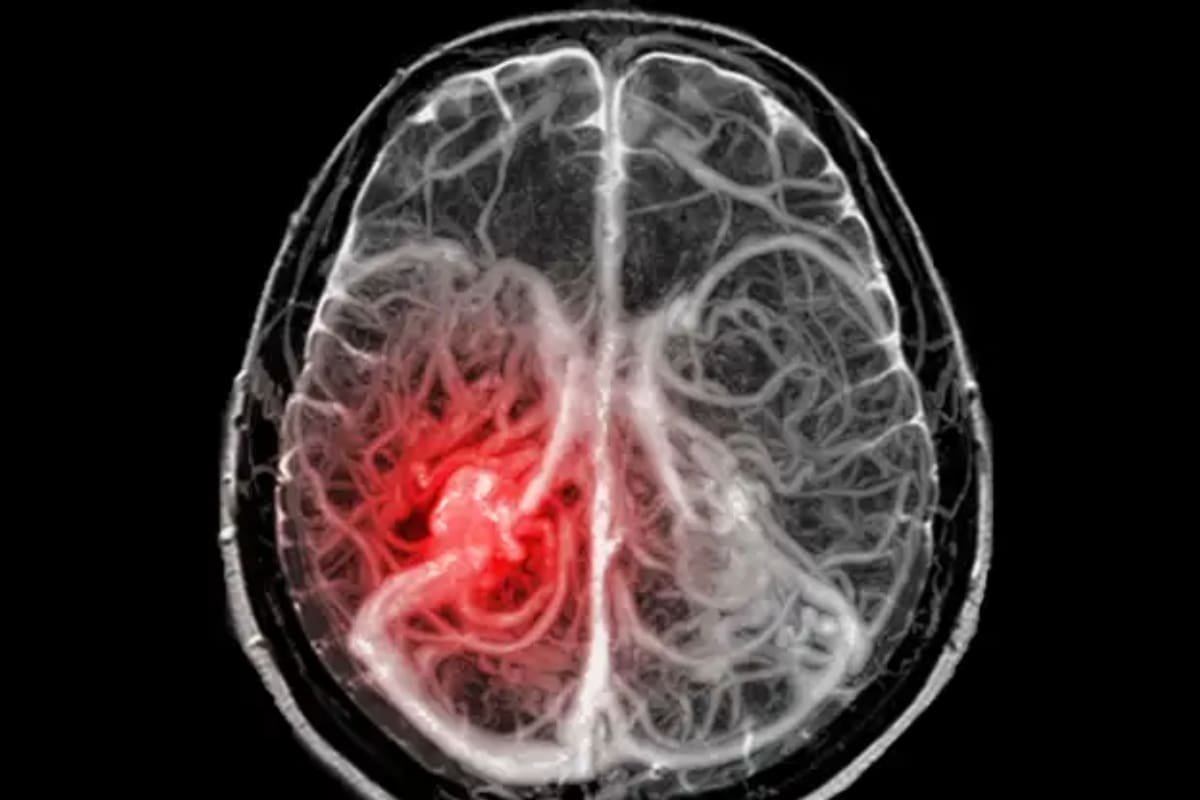

La curación, única en el mundo, de un niño con un glioma en el tronco cerebral, uno de los tipos de cáncer de cerebro pediátrico más...